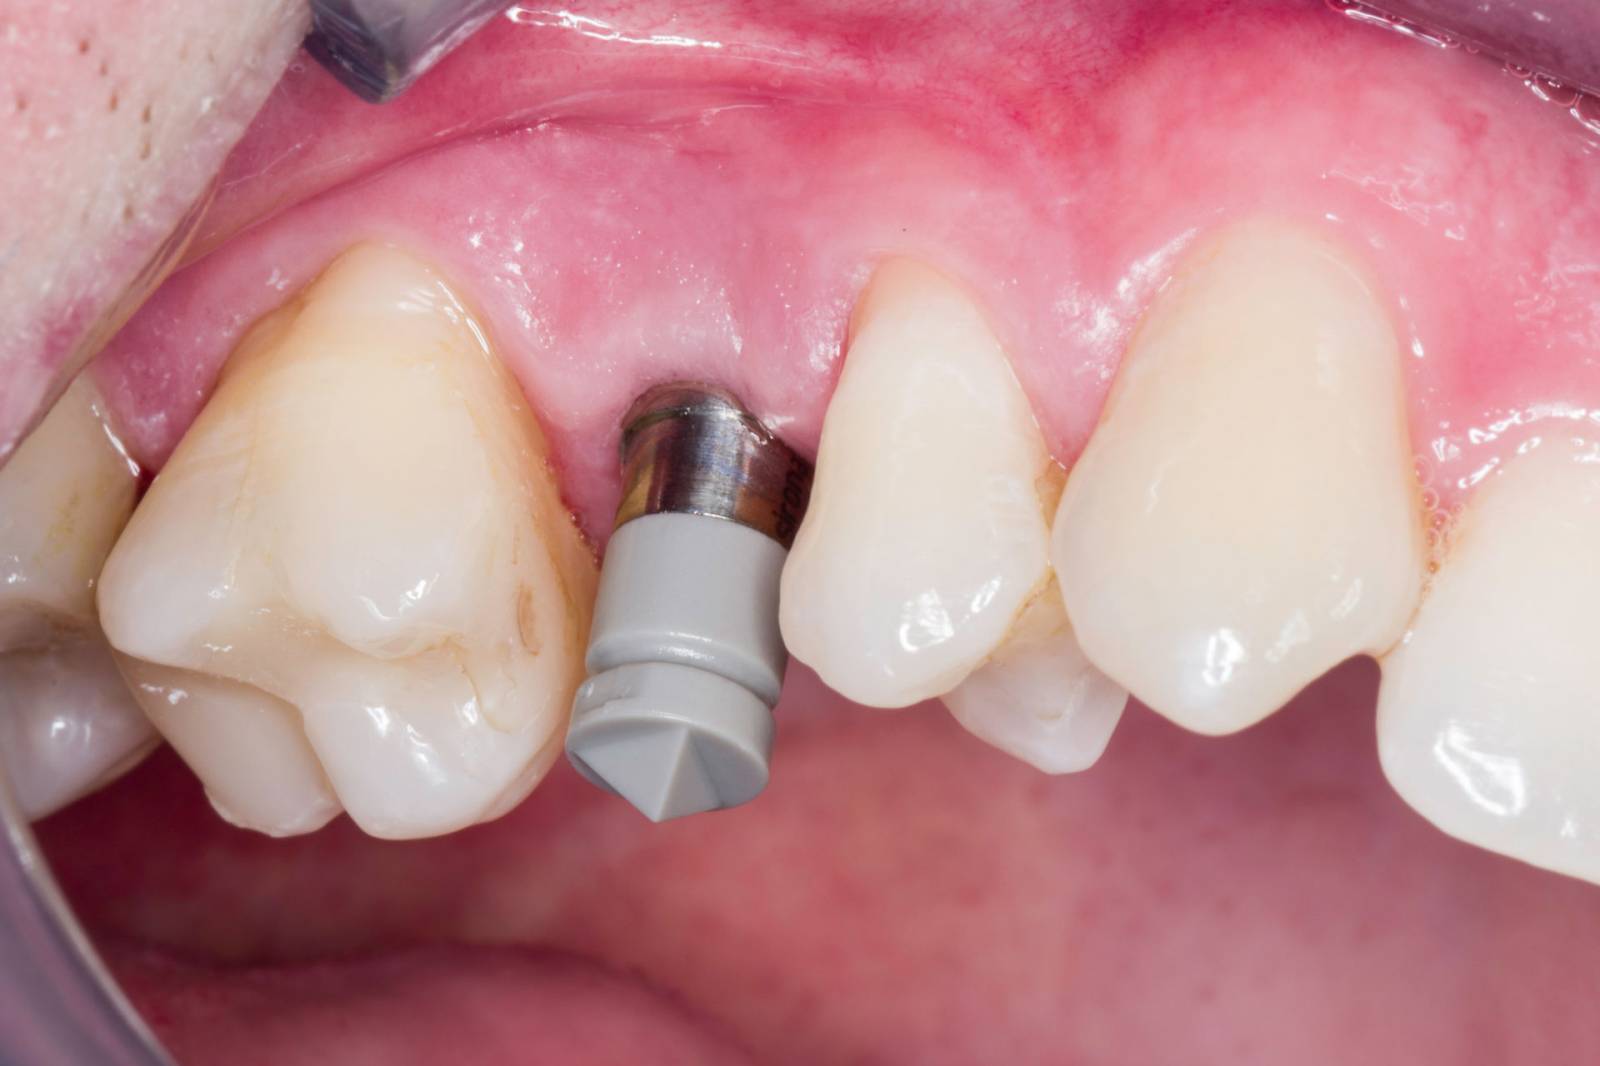

Second upper premolar

Astra Tech implant placement and an IPS e.max CAD single crown

A 36-year-old patient came to our practice four months after the extraction of tooth 15 to close the resulting tooth gap with an implant. Six months after the guided surgery, the patient presented with healthy gingiva and bone conditions.

Before: Absence of tooth 15 due to a longitudinal fracture. Patient wanted to close the resulting tooth gap.

After: A high-quality glass-ceramic crown providing a highly esthetic and long-term stable restoration.

Dr. Andreas Bindl

Zurich, Switzerland